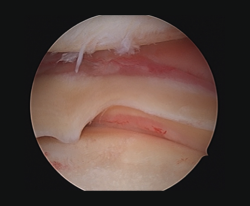

Other tests that contribute to the diagnosis are stress valgus radiographs (local anesthesia infiltration is advised in order not to underestimate the test), magnetic resonance imaging (MRI) and arthroscopic exploration (Figure 1).

Figure 1. Arthroscopic view through the anterolateral port of a positive drive-through sign with abnormal aperture of the internal compartment secondary to insufficiency of the medial collateral ligament. Right knee.